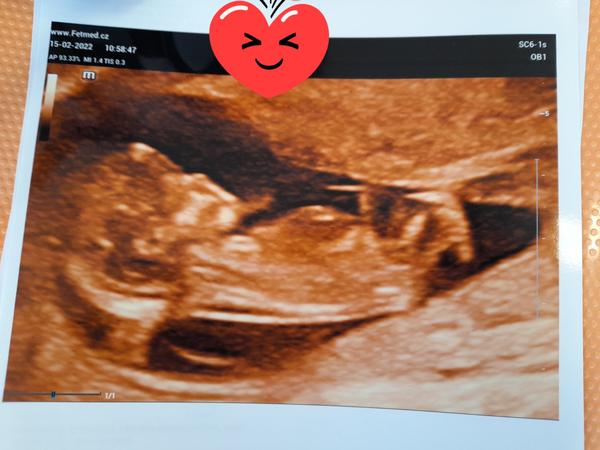

@anickaaa28 Ahojki, tak dnes kontrola a malému už tlouklo srdíčko ❤️jsem 7+1 jsem neskutečně šťastná. Zasílám fotečku naší fazolky. Dr říkal, že to je macek 😁❤️🍀také ti přeji aby vše bylo v pořádku a taky dej vědět

@anickaaa28 Ahojki, tak jak jsi dopadla na screeningu? Doufám, že všechno v pořádku ❤️ Já byla ve čtvrtek u Dr, malý roste nádherně. Už máme 3.5 cm🙂 1.3. jdu také na screening tak taky jsem nervózní ale věřím, že vše bude v pořádku. Posílám zase fotečku. A dej vědět ju o sobě 🙂🍀 Pa Veru